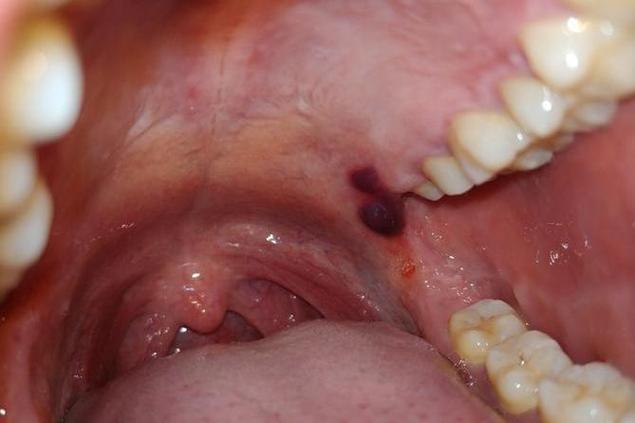

口腔里的“血泡”最常见的是两种:创伤性血疱 和 粘液囊肿(含血性),它们的形态和成因不同。

创伤性血疱

- 成因: 最常见的原因,通常是不小心咬到(尤其是腮帮子内侧、嘴唇内侧)、吃硬物(如薯片、坚果壳)、烫伤、或刷牙用力过猛等导致口腔黏膜下的毛细血管或小血管破裂出血,血液积聚在黏膜下层形成。

- 外观描述:

- 位置: 最常见于软腭、颊黏膜(腮帮子内侧)、唇内侧等容易被咬到的部位,舌侧缘也可能发生。

- 形态: 通常是圆形或椭圆形的隆起,边界清晰。

- 颜色: 刚形成时是鲜红色或暗红色,像一个小血球,随着时间推移(几小时到一天内),血液可能部分凝固,颜色会变成暗紫色、蓝紫色甚至深褐色。

- 大小: 大小不一,小的如米粒,大的可能像一元硬币或更大。

- 内容物: 泡内充满液体血液,摸上去柔软、有波动感(像水泡,但里面是血),如果泡壁很薄,有时能看到里面流动的血液。

- 周围黏膜: 通常周围黏膜是正常的,没有明显红肿(除非合并感染)。

- 感觉: 通常不痛或只有轻微胀痛感,除非位置特别敏感或反复摩擦刺激,有时在咬伤的瞬间会感到刺痛。

- 演变: 血泡通常在1-3天内会自行破裂,破裂后,血液流出,留下一个边缘不规则的浅表溃疡面,溃疡面可能比较痛(尤其是进食时),但通常会在1-2周内自行愈合,不留疤痕。